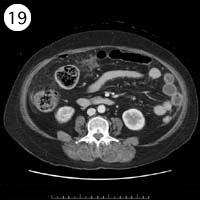

19

57歳 女性